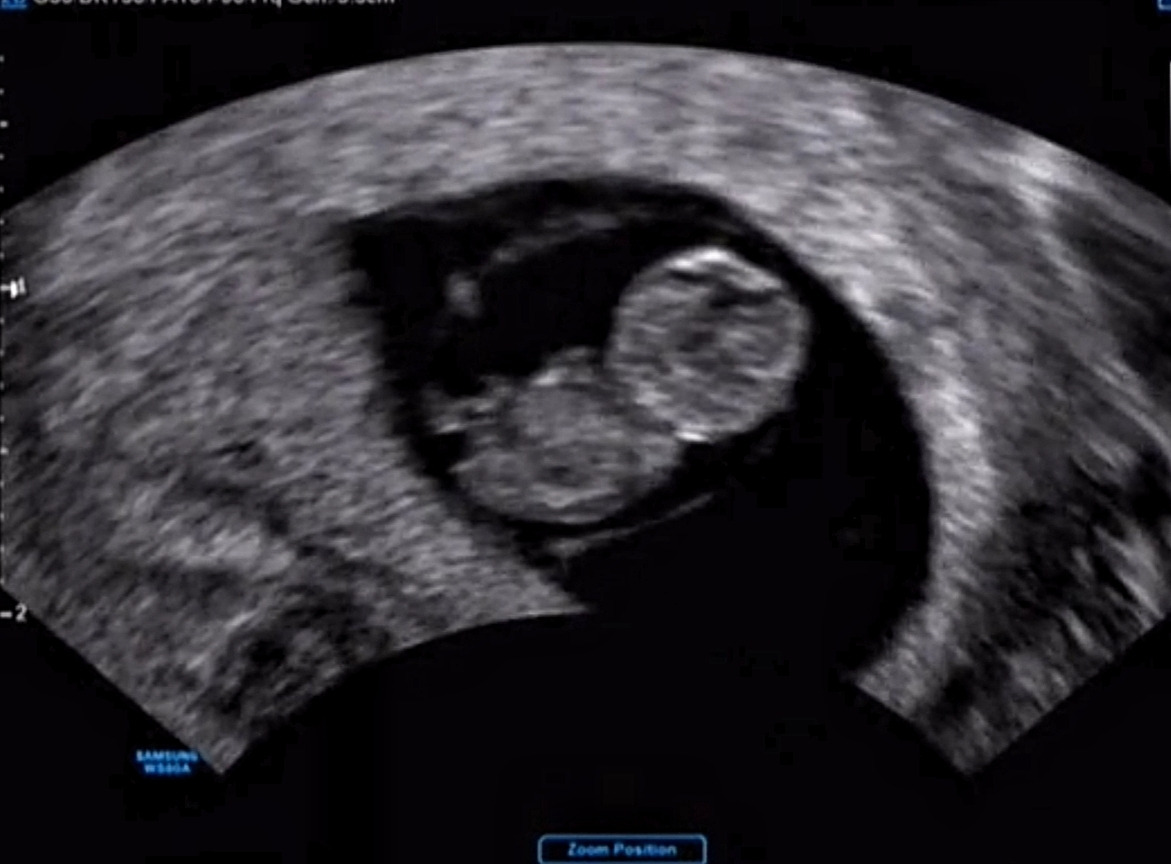

안녕, 아가? 임신 8주, 완벽하게 '젤리 곰'을 연출하고 있는 나의 '아기 효동'